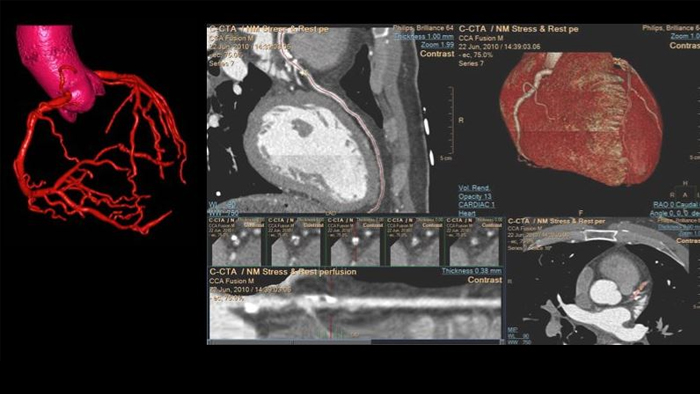

Wir zeigen, wie Bildgebungstechnologien durch ausgezeichnete Qualität bei der diagnostischen Bildgebung, mittels Analysen, Berichterstellung und durch Einblicke über verschiedene Bildgebungsmodalitäten hinweg lebensverändernde klinische Erkenntnisse für Patienten und kardiologische Behandlungsteams bieten. Dabei unterstützen sie gleichzeitig die Arbeitsabläufe, Effizienz und Zufriedenheit der Mitarbeiter.

Prüfen, analysieren und quantifizieren Sie klinische Daten von verschiedenen Modalitäten und für unterschiedliche klinische Indikationen mit KI-gestützten 3D-Modellen, Kartendarstellungen und anderen Quantifizierungsfunktionen.

Stellen Sie einen einzigen Zugriffspunkt für die kardiovaskulären Diagnosefunktionen und Bilder mehrerer Modalitäten des Patienten in voller diagnostischer Qualität zur Verfügung, einschließlich vorheriger Untersuchungen, Befunde, Messungen und Berichte.

Ermöglicht eine höhere Effizienz bei der Ansicht, Analyse und Berichterstellung, indem es Behandlungsteams die Flexibilität gibt, je nach aktuellen und zukünftigen Anforderungen unterschiedliche Arbeitsabläufe anzuwenden.